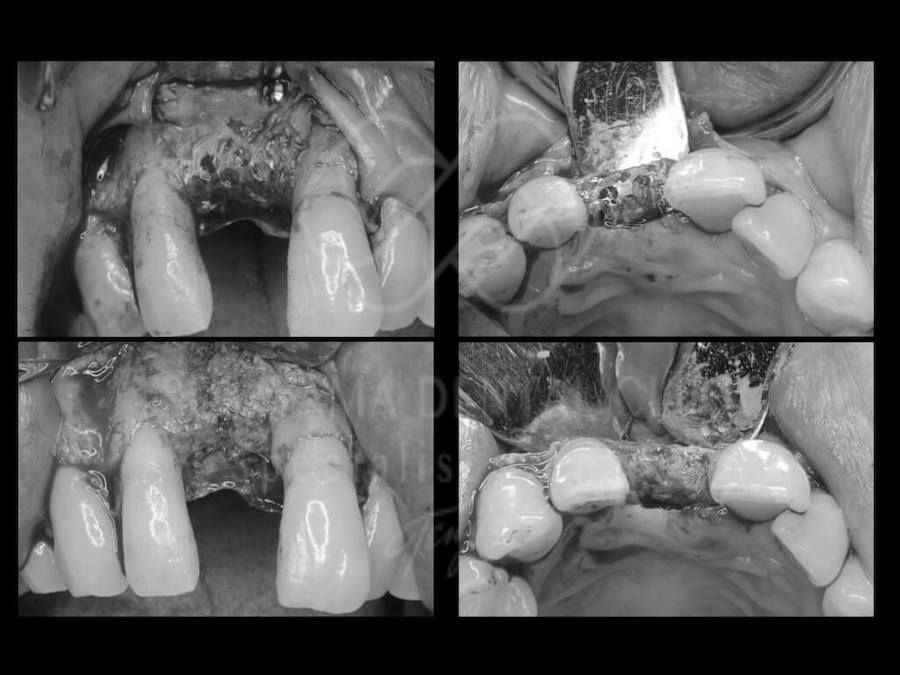

治療中